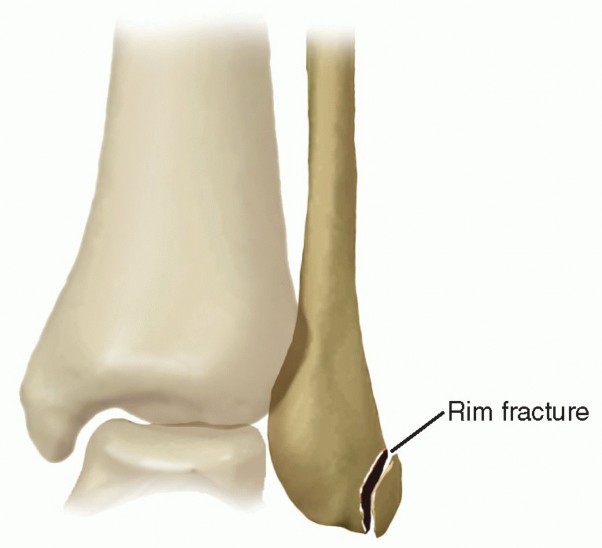

Bony procedures attempt to recreate a more stable fibular sulcus by deepening the fibular groove or extending the fibular rim. In this chapter, we present a soft tissue augmentation procedure using a periosteal-based flap of the retrofibular sulcus.

| An Eckert and Davis grade 3 fracture, with a thin fragment of bone along the cartilaginous lip attached to the deep surface of the peroneal retinaculum; the anterior portion of the SPR is already compromised and would not make a good surgical candidate. | |||

| Routine ankle radiographs are essential to identify or rule out a rim fracture of the distal fibula, which occurs in 15% to 50% of all cases of peroneal subluxation.1 | |||